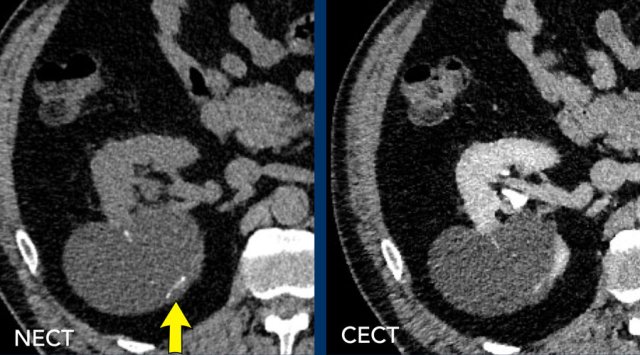

MRI of the same patient.

The lesion is hypointense on T2WI and hyperintense on T1WI.

There is no contrast enhancement on the subtraction sequence.

On MRI the lesion could be confirmed as Bosniak II.